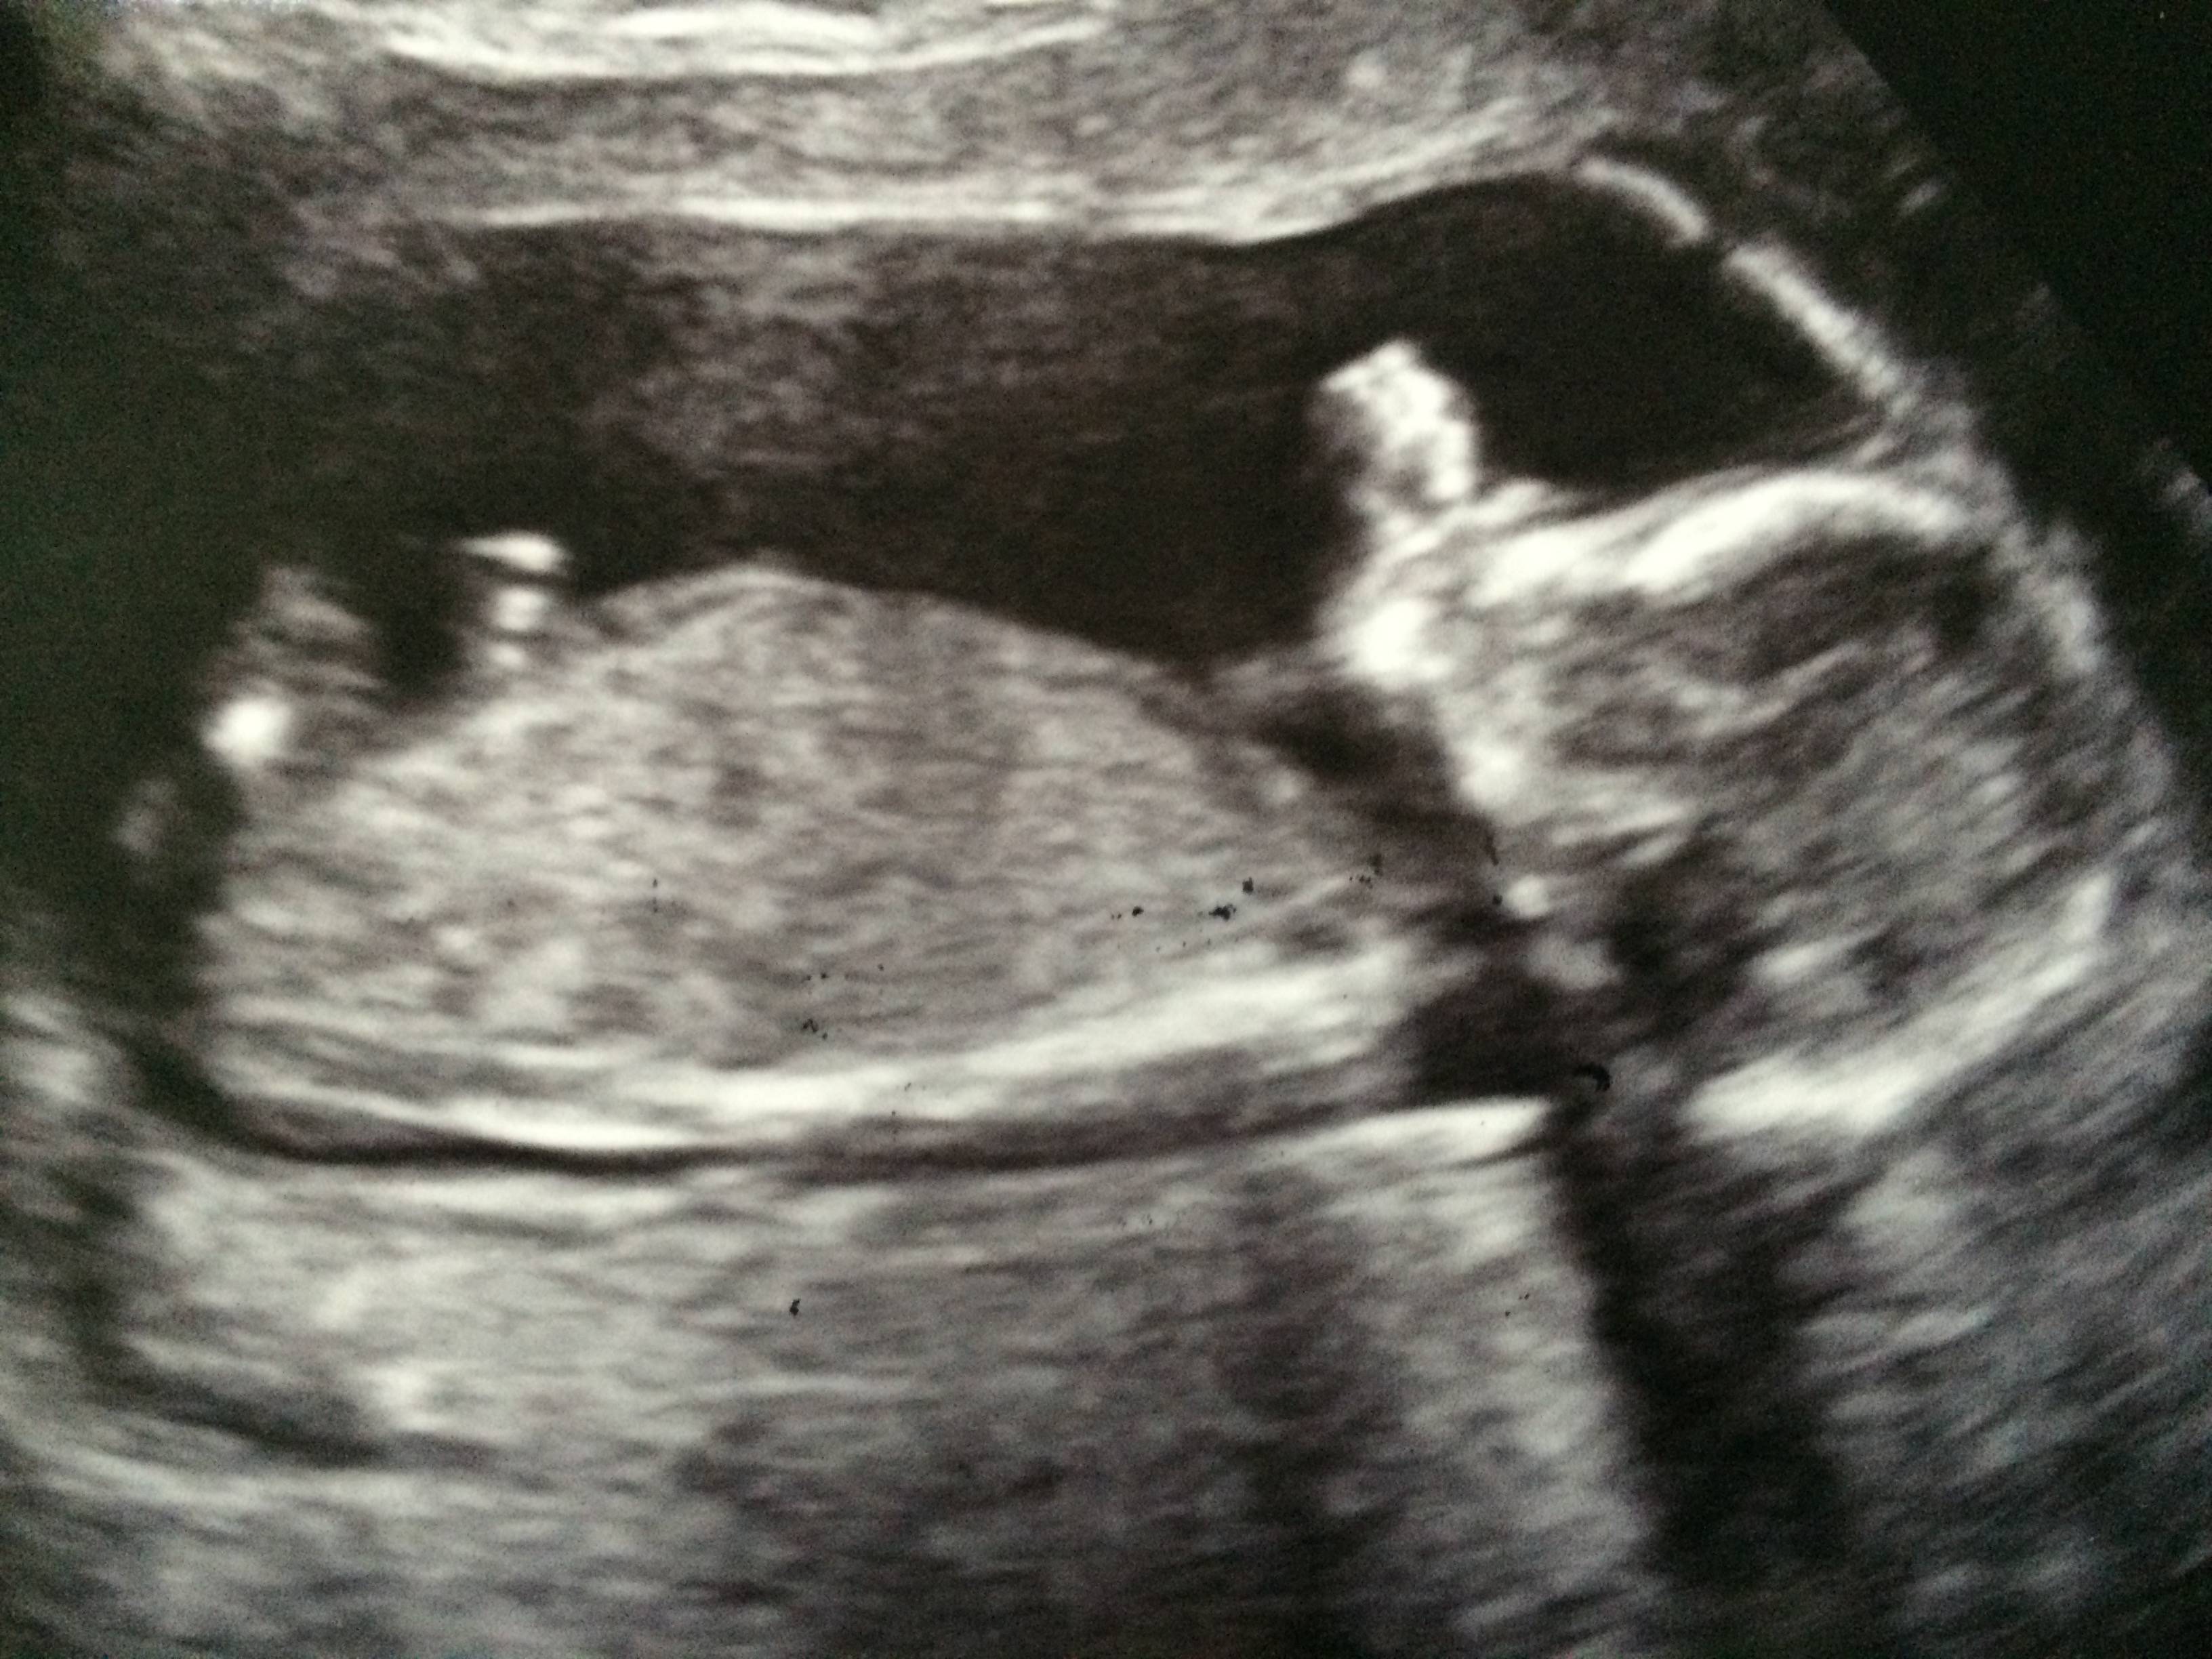

Is there a nub visible here? Thanks :) Attachment 31468

I don't think I can see anything sorry

I don't see a nub either

Any other pics? It looks like baby is rolling to the side.